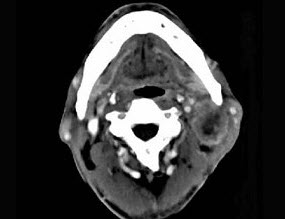

- 单项选择题65岁男性,吸烟史30余年,近半年来颈部出现疼痛性肿块,CT扫描如图所示,请选择最可能诊断()。

- D